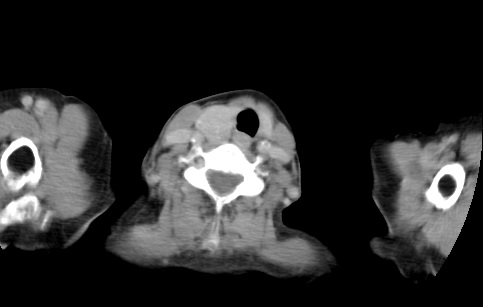

标题: CT23982:女67岁,胸部扫描时发现,甲状腺瘤? [打印本页]

标题: CT23982:女67岁,胸部扫描时发现,甲状腺瘤?

右侧甲状腺腺瘤!支持!不排除甲状腺癌可能!建议手术切除!

右侧甲状腺占位性病变,性质待定(甲状腺腺瘤?);建议:必要时行进一步检查。

右侧甲状腺占位性病变,性质待定(甲状腺腺瘤?);建议穿刺活检。

右侧甲状腺占位性病变,甲状腺腺瘤可能,建议穿刺活检。